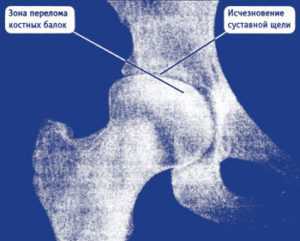

Снимок 3. Здесь представлен снимок пациентки, которой диагноз «коксартроз» поставили вовремя, еще на первой стадии болезни. Но, несмотря на своевременно поставленный серьезный диагноз, сама пациентка очень безалаберно отнеслась к своему здоровью и 5 лет игнорировала назначенное врачами правильное лечение. Вот что представлял ее сустав через 5 лет:

- суставной хрящ разрушен почти полностью (нет расстояния между костями, головка бедренной кости почти полностью «вклинилась» в вертлужную впадину);

- головка бедренной кости сильно деформирована, цвет верхней части головки на рентгене выглядит светлее (признак микроперелома костных балок из-за повышенного давления на верхнюю часть головки).

Коксартроз 3-й стадии. Фотография из архива доктора Евдокименко

Все эти рентгенологические признаки соответствуют коксартрозу третьей стадии. Третья стадия коксартроза была также подтверждена во время осмотра пациентки. К сожалению, из-за того, что пациентка халатно отнеслась к своему здоровью и не стала лечиться вовремя, ей пришлось идти на операцию по замене тазобедренного сустава.